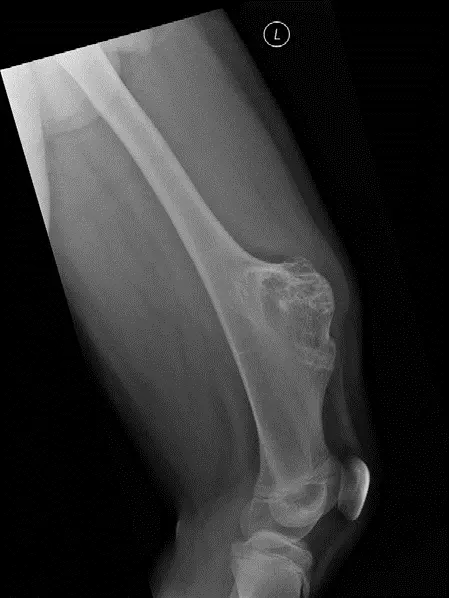

تنشأ معظم الأورام العظمية الغضروفية في منطقة الكردوس (Metaphysis)، وهي الجزء من العظم الطويل القريب من صفيحة النمو (Physis). ومن المثير للاهتمام أن هذه الأورام تميل إلى النمو بعيدًا عن المفصل المجاور، وهو ما يمكن ملاحظته بوضوح في صور الأشعة السينية.

التصوير بالأشعة السينية X-ray

تُعد الأشعة السينية (X-ray) هي الخطوة التشخيصية الأولية والأكثر أهمية للورم العظمي الغضروفي. تظهر الأشعة السينية الورم كـ "نتوء عظمي" يبرز من سطح العظم. السمة التشخيصية المميزة التي تؤكد التشخيص وتفرق الورم العظمي الغضروفي عن الأورام السطحية الأخرى هي "علامة الاستمرارية" (Continuity sign)، حيث تظهر قشرة العظم (Cortex) ونخاع العظم (Medulla) للورم مستمرة مع قشرة ونخاع العظم الأم. كما تظهر الأشعة السينية أن الورم ينمو عادةً بعيدًا عن المفصل المجاور.